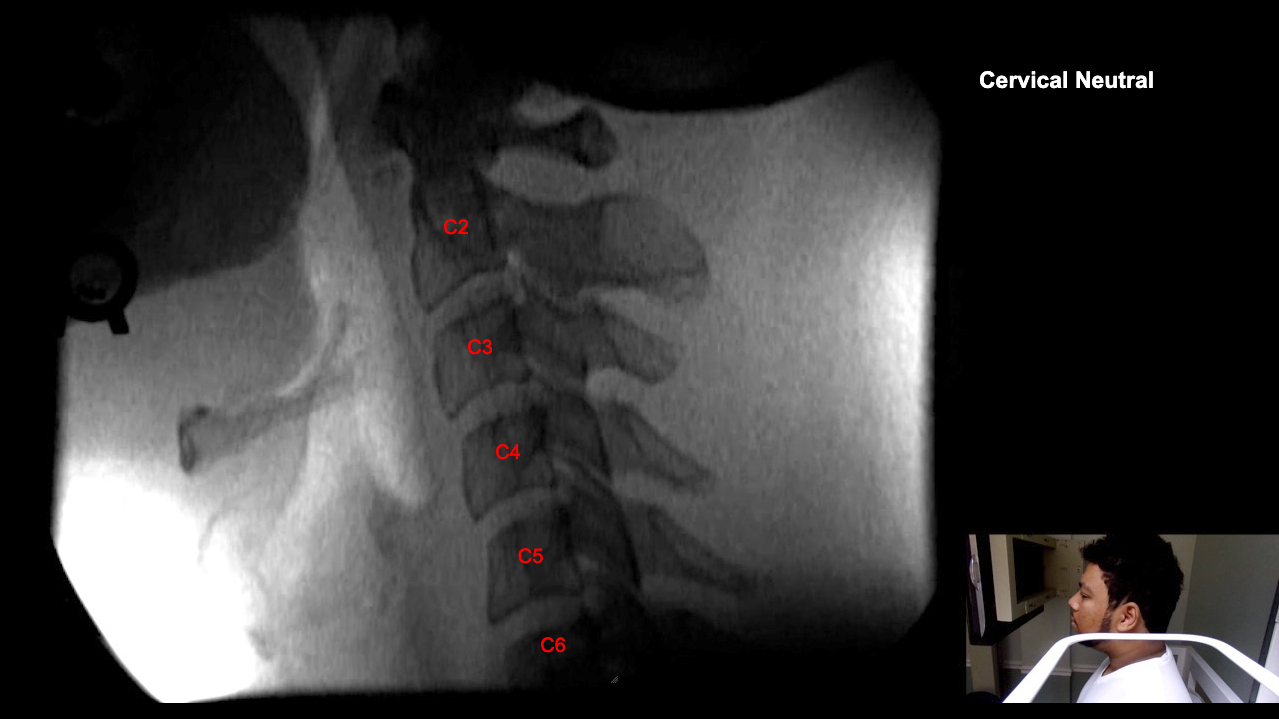

Image Name Image Type Image